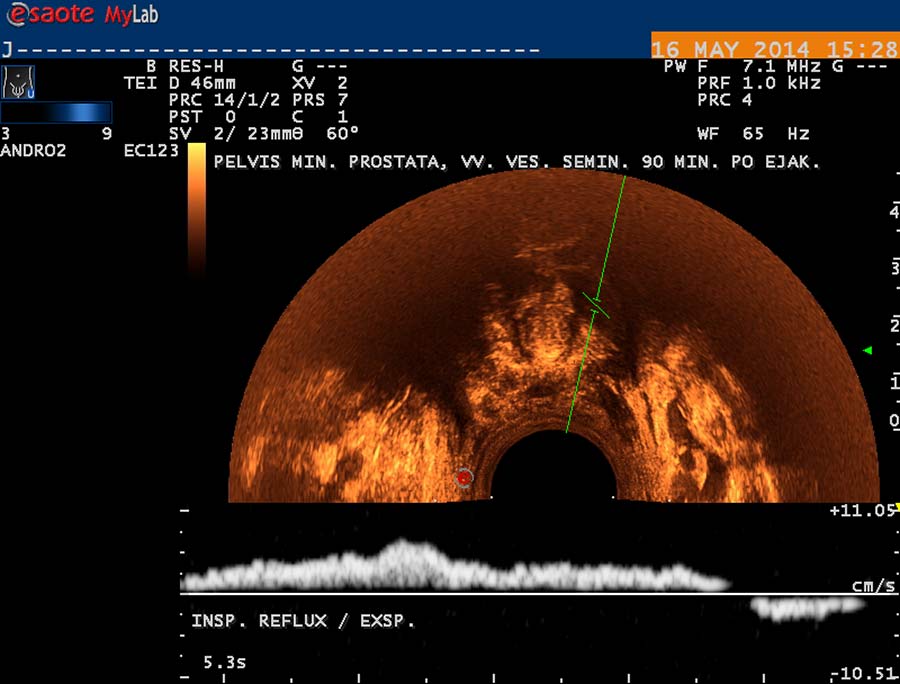

USG diagnostika vyžaduje odpovídající vybavení (obr. 12), zkušenosti a dostatek času. Vyšetření USG provádíme po termografickém vyšetření, na lůžku vyhřívaném na 30 st. Celsia, ultrasonografický gel zahříváme ve vodní lázni na teplotu 35 stupňů. Chladová kontrakce musculus cremaster vede k falešně negativním nálezům. Základní projekcí je koronární sken varlete (obr. 14) následovaný volumometrií ve dvou rovinách (obr. 15). Již na těchto skenech varlete je patrné rozšíření intratestikulárních cév, lépe je však viditelné při harmonickém („tissue enhancement imaging – TEI“) zobrazení (obr. 16, 17), a při barevném Dopplerovském zobrazení (Power Doppler) s TEI (obr. 18) s měřením šíře stěny a lumen žíly. Objemné dilatované žíly pampiniformního plexu jsou velmi dobře patrné na kolorizovaném TEI zobrazení (obr. 19), kde je možné zachytit pohyb venózní krve v souvislosti s dechem, intraabdominálním (IAP) a intrathorakálním tlakem. Informaci o atrofizaci tkáně získáme ze záznamu deformace kontury tunica albuginea podložkou, kterou je měkká buničina vložená pod skrotum (obr. 20, obr. 21 s volumometrií). Triplexní Dopplerovský záznam umožní hodnotit délku žilního refluxu a rychlost proudu refluktující krve v inspiriu, reflux při zvýšení intraabdominálního tlaku (obr. 22,23). Duplexní Dopplerovský záznam při harmonickém zobrazení s kolorizací zachycuje senzitivně změnu rychlosti proudění při refluxu v inspiriu s navazujícím zvýšením rychlosti při IAP (obr 25). Významná je možnost zachycení refluxu při klidném dýchání (respirační reflux, obr. 26).

V případě druhém jde o kompresi ilických žil, které drénují vény z varlat probíhající podél chámovodů, a vény kremasterické, ústící do pánevních žilních pletení. Průběh žilní je však interindividuálně variabilní. Pleteň žilní pod bazí močového měchýře a okolo prostaty ( plexus venosus - labyrinthus Santorini) je velmi dobře vyšetřitelná transrektální USG. Používáme sondu o frekvenci 9 MHz se stejnými možnostmi harmonického zobrazení a Dopplerovské diagnostiky jako při vyšetření testes. Vény v okolí prostaty jsou dobře patrné v transverzální projekci na obr. 28, jejich ventrokaudální konvergence před prostatu je patrná na obr. 29, subprostatický průběh žil na obr. 30. Respirační reflux do těchto pletení je patrný na duplexním Dopplerovském záznamu – obr. 31, reflux v inspiriu a odtok v exspiriu na obr. 32. V kolmé projekci je patrný reflux při klidovém dýchání a při hlubším inspiriu na obr. 33. Přínos této diagnostiky pánevní žilní hypertenze bude v budoucnu užitečný při hodnocení žilní drenáže prostaty a žilní hypertenze v oblasti plexus venosus Santorini v souvislosti s významem hladin testosteronu a dihydrotestosteronu pro prostatu. Hladiny androgenů jsou v drenážní oblasti spermatických vén vyšší, nežli v periferní krvi.

obr. 31

obr. 32

obr. 33